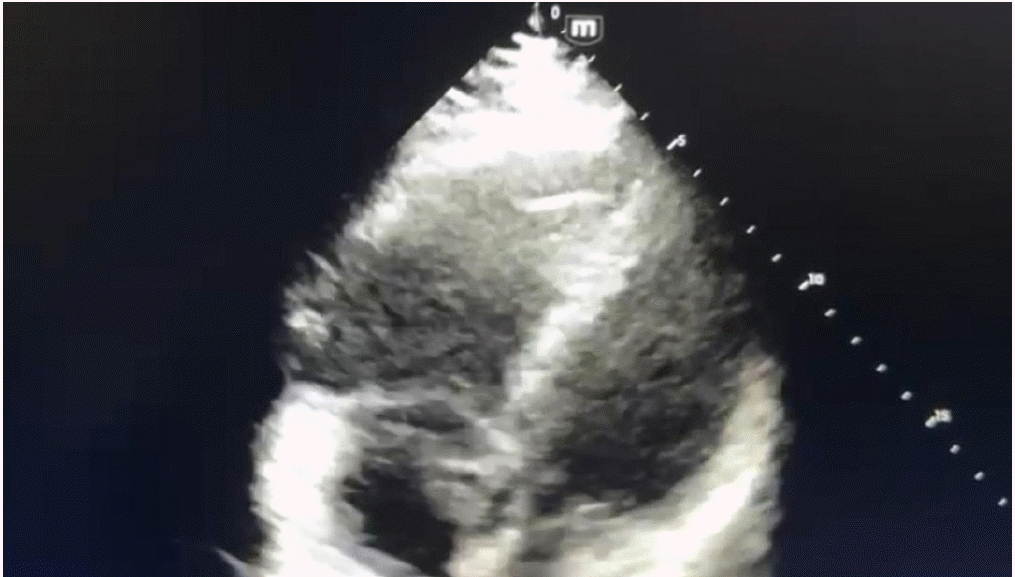

In view of severe respiratory distress and worsening hemodynamic status, he was intubated, and vasopressor commenced after fluid resuscitation. Computed tomography brain, chest and abdomen without contrast were done in view of high creatinine which revealed hemorrhagic brain contusion in the right posterior parietal and left higher parietal lobes. Two-dimensional echocardiography revealed severely dilated right atrium and right ventricle, jerky inter-ventricular septum with shift toward left ventricle, severe right ventricular dysfunction, and normal left ventricular systolic function (Figures 1-3). The lower extremity venous doppler showed evidence suggestive of thrombosis in bilateral superior femoral veins and left popliteal vein. Arterial blood gas analysis revealed nearly compensated metabolic acidosis with high lactate and hyperglycemia. On admission, lab include D-dimer of >20,000 ng/ml, serum creatinine 2.3 mg/dl, white blood cell counts 13,600 per microliter with normal hemoglobin and platelets counts, prothrombin time (PT) 23.1 seconds, international normalized ratio 1.7, and activated partial thromboplastin time (aPTT) 59.5 seconds. Liver function test revealed mildly elevated alanine transaminase and aspartate transferase (161 and 137 unit, respectively).